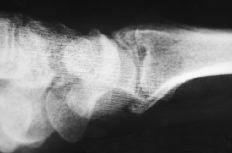

Figura 4. Radiografía posteroanterior de muñeca donde se muestra una luxación cubital del implante junto con un colapso carpiano y una traslación cubital.

Hubo dos luxaciones del implante hacia cubital, subluxación en otros dos, una palmar y otra dorsal, y presencia de DISI en seis y de VISI en dos. La siliconitis e imágenes líticas intraóseas (de predominio hueso grande-ganchoso) se dieron en ocho pacientes y la artropatía degenerativa radiocarpiana e intercarpiana en 10. Se realizaron reintervenciones en cuatro pacientes: tres artrodesis del carpo y una resección de la primera fila.

Debido a esta falta del implante hemos observado en un 20% de los casos luxación y subluxación de la artroplastia, en un 30% inestabilidad en DISI y en un 10% en VISI. La incidencia de imágenes líticas intraóseas y sinovitis por liberación de partículas de silicona en nuestra serie es del 40%. Surgen por la abrasión y el desgaste del implante y producen una sinovitis hipertrófica con granulomas por silicona.19 Microscópicamente se aprecia la respuesta del huésped a estas partículas como una reacción de células gigantes a cuerpo extraño. Los leucocitos y macrófagos fagocitan el material, pero la silicona no se afecta por las enzimas lisosomales, lo que induce una sinovitis reactiva que no es exclusiva de la silicona (PMMA, polietileno y otros materiales metálicos), estando siempre en relación con el tamaño de la partícula. Las partículas de silicona son de 30 a 60 micras de diámetro. Estos implantes se han desaconsejado para la sustitución del escafoides y del semilunar, ya que al estar sometidos a importantes cargas de compresión se produce su fragmentación.31 Los factores que desgastan el implante de silicona y contribuyen a la formación de partículas son las fuerzas excesivas a través del implante debidas a la asociación de inestabilidad o de colapso, una malposición o exceso de tamaño, exceso de movilidad y abuso de la actividad diaria.43,44